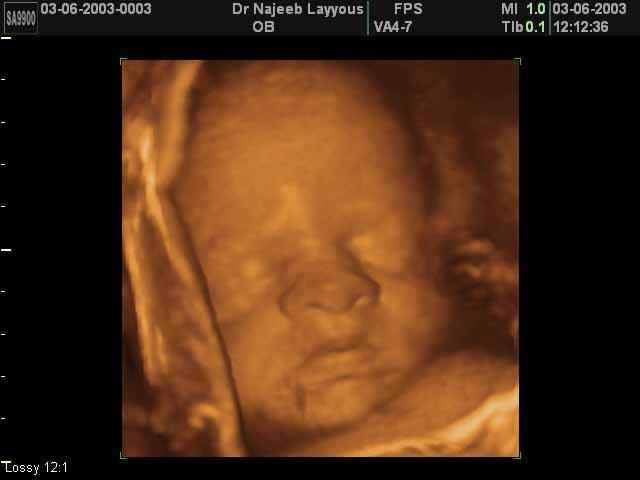

صور لوجه الجنين بجهاز الالتراساوند ثلاثي الأبعاد | الدكتور نجيب ليوس

صور لوجه الجنين بجهاز الموجات فوق صوتية ثلاثي الأبعاد